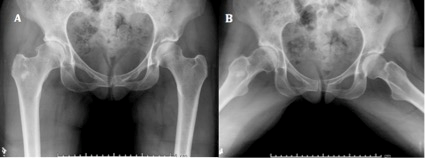

Figura 3: Radiografías preoperatorias de ambas caderas de paciente femenina de cincuenta y seis años. A) Frente: se puede observar la esclerosis subcondral y osteofito medial, los cuales son elementos predictivos de pobres resultados. B) Se constata el aplanamiento del cuello femoral.